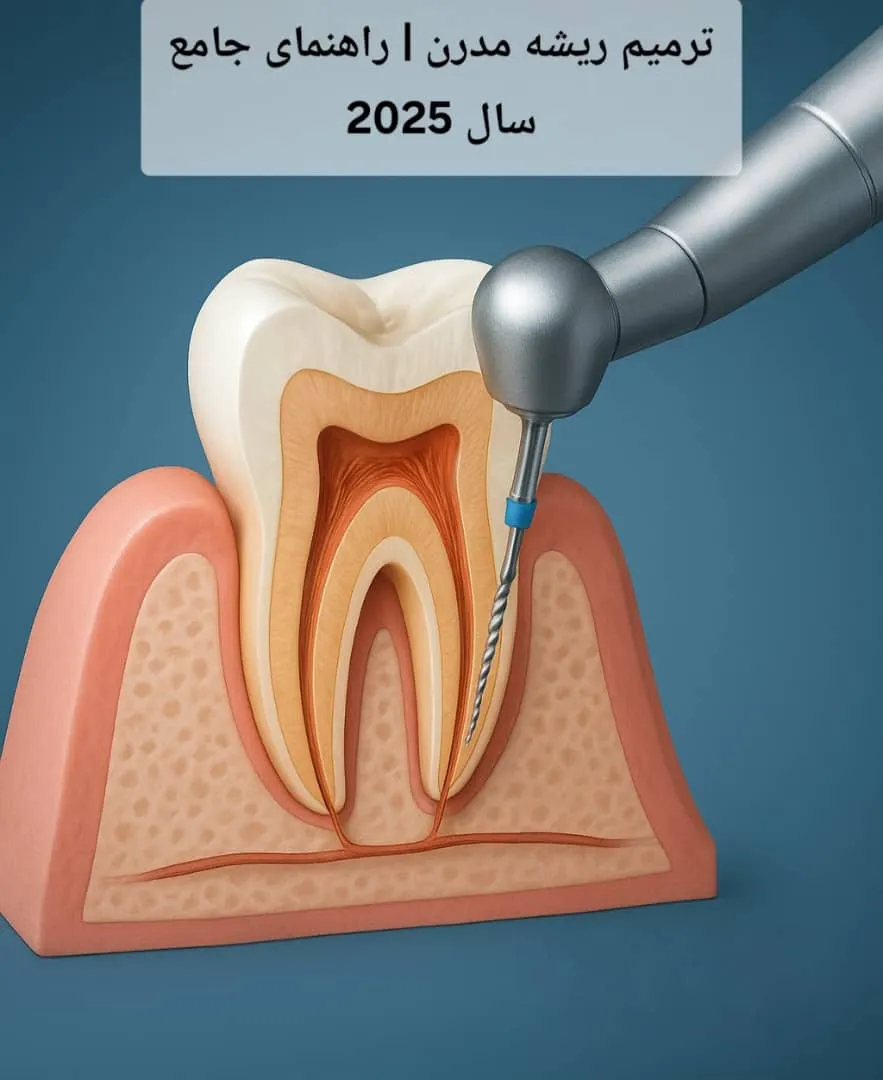

پیش از آنکه وارد مبحث ترمیم ریشه مدرن شویم، بهتر است مفهوم پایهای درمان ریشه را مرور کنیم. زمانی که پوسیدگی دندان به عمق زیادی نفوذ کرده و به پالپ (عصب) دندان میرسد، التهاب یا عفونت ایجاد میشود. در این حالت دندانپزشک با انجام درمان ریشه، بافت عصبی آلوده را خارج کرده و فضای داخلی دندان را ضدعفونی و پر میکند.

ترمیم ریشه مدرن مجموعهای از روشها و فناوریهای پیشرفته است که هدف آن بهبود دقت، کاهش درد، کوتاهتر شدن زمان درمان و افزایش ماندگاری نتایج است. در این روشها، از ابزارهای دیجیتال، میکروسکوپهای دندانی، سیستمهای التراسونیک، مواد زیستی پیشرفته و دستگاههای هوشمند برای پاکسازی و پر کردن کانالهای ریشه استفاده میشود.

در ترمیم ریشه مدرن از بیحسیهای موضعی نسل جدید و ابزارهای تزریق دقیق استفاده میشود که موجب میشود بیمار حتی کوچکترین درد یا سوزش را احساس نکند. سیستمهای دیجیتال تزریق بیحسی مانند The Wand این کار را بهصورت کنترلشده انجام میدهند. - دسترسی و پاکسازی کانال با میکروسکوپ دندانی

یکی از پیشرفتهای بزرگ در ترمیم ریشه مدرن، استفاده از میکروسکوپ جراحی دندانپزشکی است. این ابزار به دندانپزشک اجازه میدهد تا کانالهای ریشه را تا چند برابر بزرگنمایی ببیند و پاکسازی دقیقتری انجام دهد.

در این مرحله از ابزارهای نیکل-تیتانیوم انعطافپذیر برای تمیز کردن کانال استفاده میشود. - شستوشو با سیستمهای التراسونیک و ضدعفونی کامل